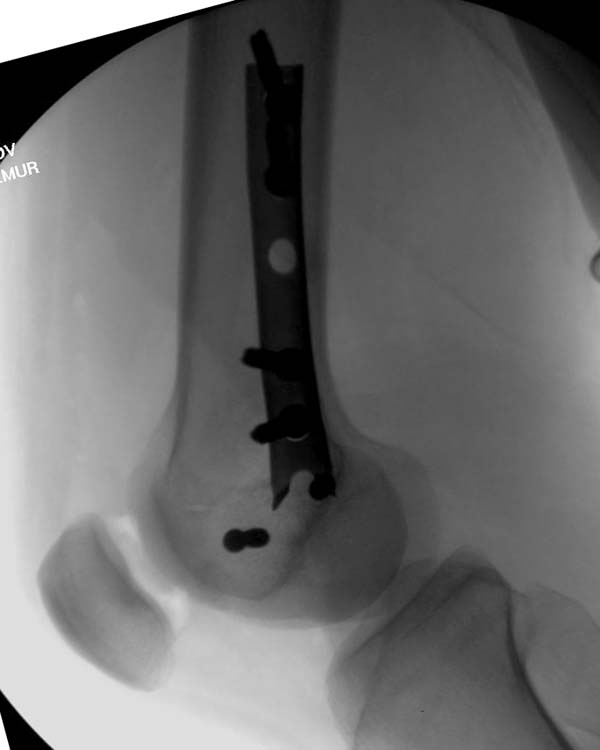

Остеосинтез LCP пластиной

В данном случае предпочтителен парапателлярный доступ, где необходимо создать лучший обзор к мыщелку. После остеотомии и репозиции фиксацию надо проделать поперечными винтами и дополнительно задней antiglade plate - сделанной из 1/3 tubular plate.

Здесь представлены различные варианты фиксации перелома, а также снимки комбинации перелома с повреждением хряща (12-19). Пластика хряща OsseoFit и установка custom made plate.